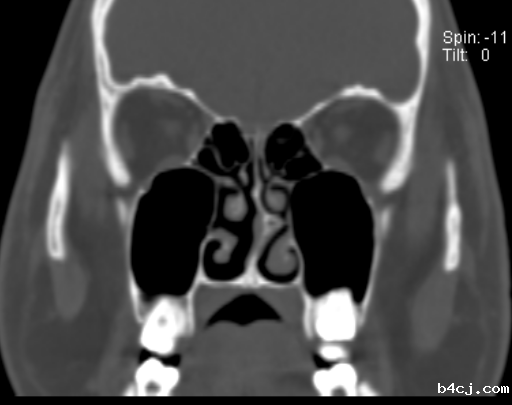

哪些患者适合行外科治疗呢?一,经规范化药物治疗和(或)免疫治疗,鼻塞和流涕等症状无改善,有明显体征,影响生活质量;二,鼻腔有明显的解剖学变异伴功能障碍,比如鼻甲肥大、鼻中隔偏曲。伴有鼻中隔偏曲的常年性过敏性鼻炎患者,采用鼻内镜下鼻中隔偏曲矫正手术,疗效显著。

外科治疗的手术种类有哪些呢?一是主要以改善鼻腔通气功能为目的的下鼻甲减容术、鼻中隔偏曲矫正术;二是以降低鼻黏膜高反应性为目的的选择性神经切断或阻断术。